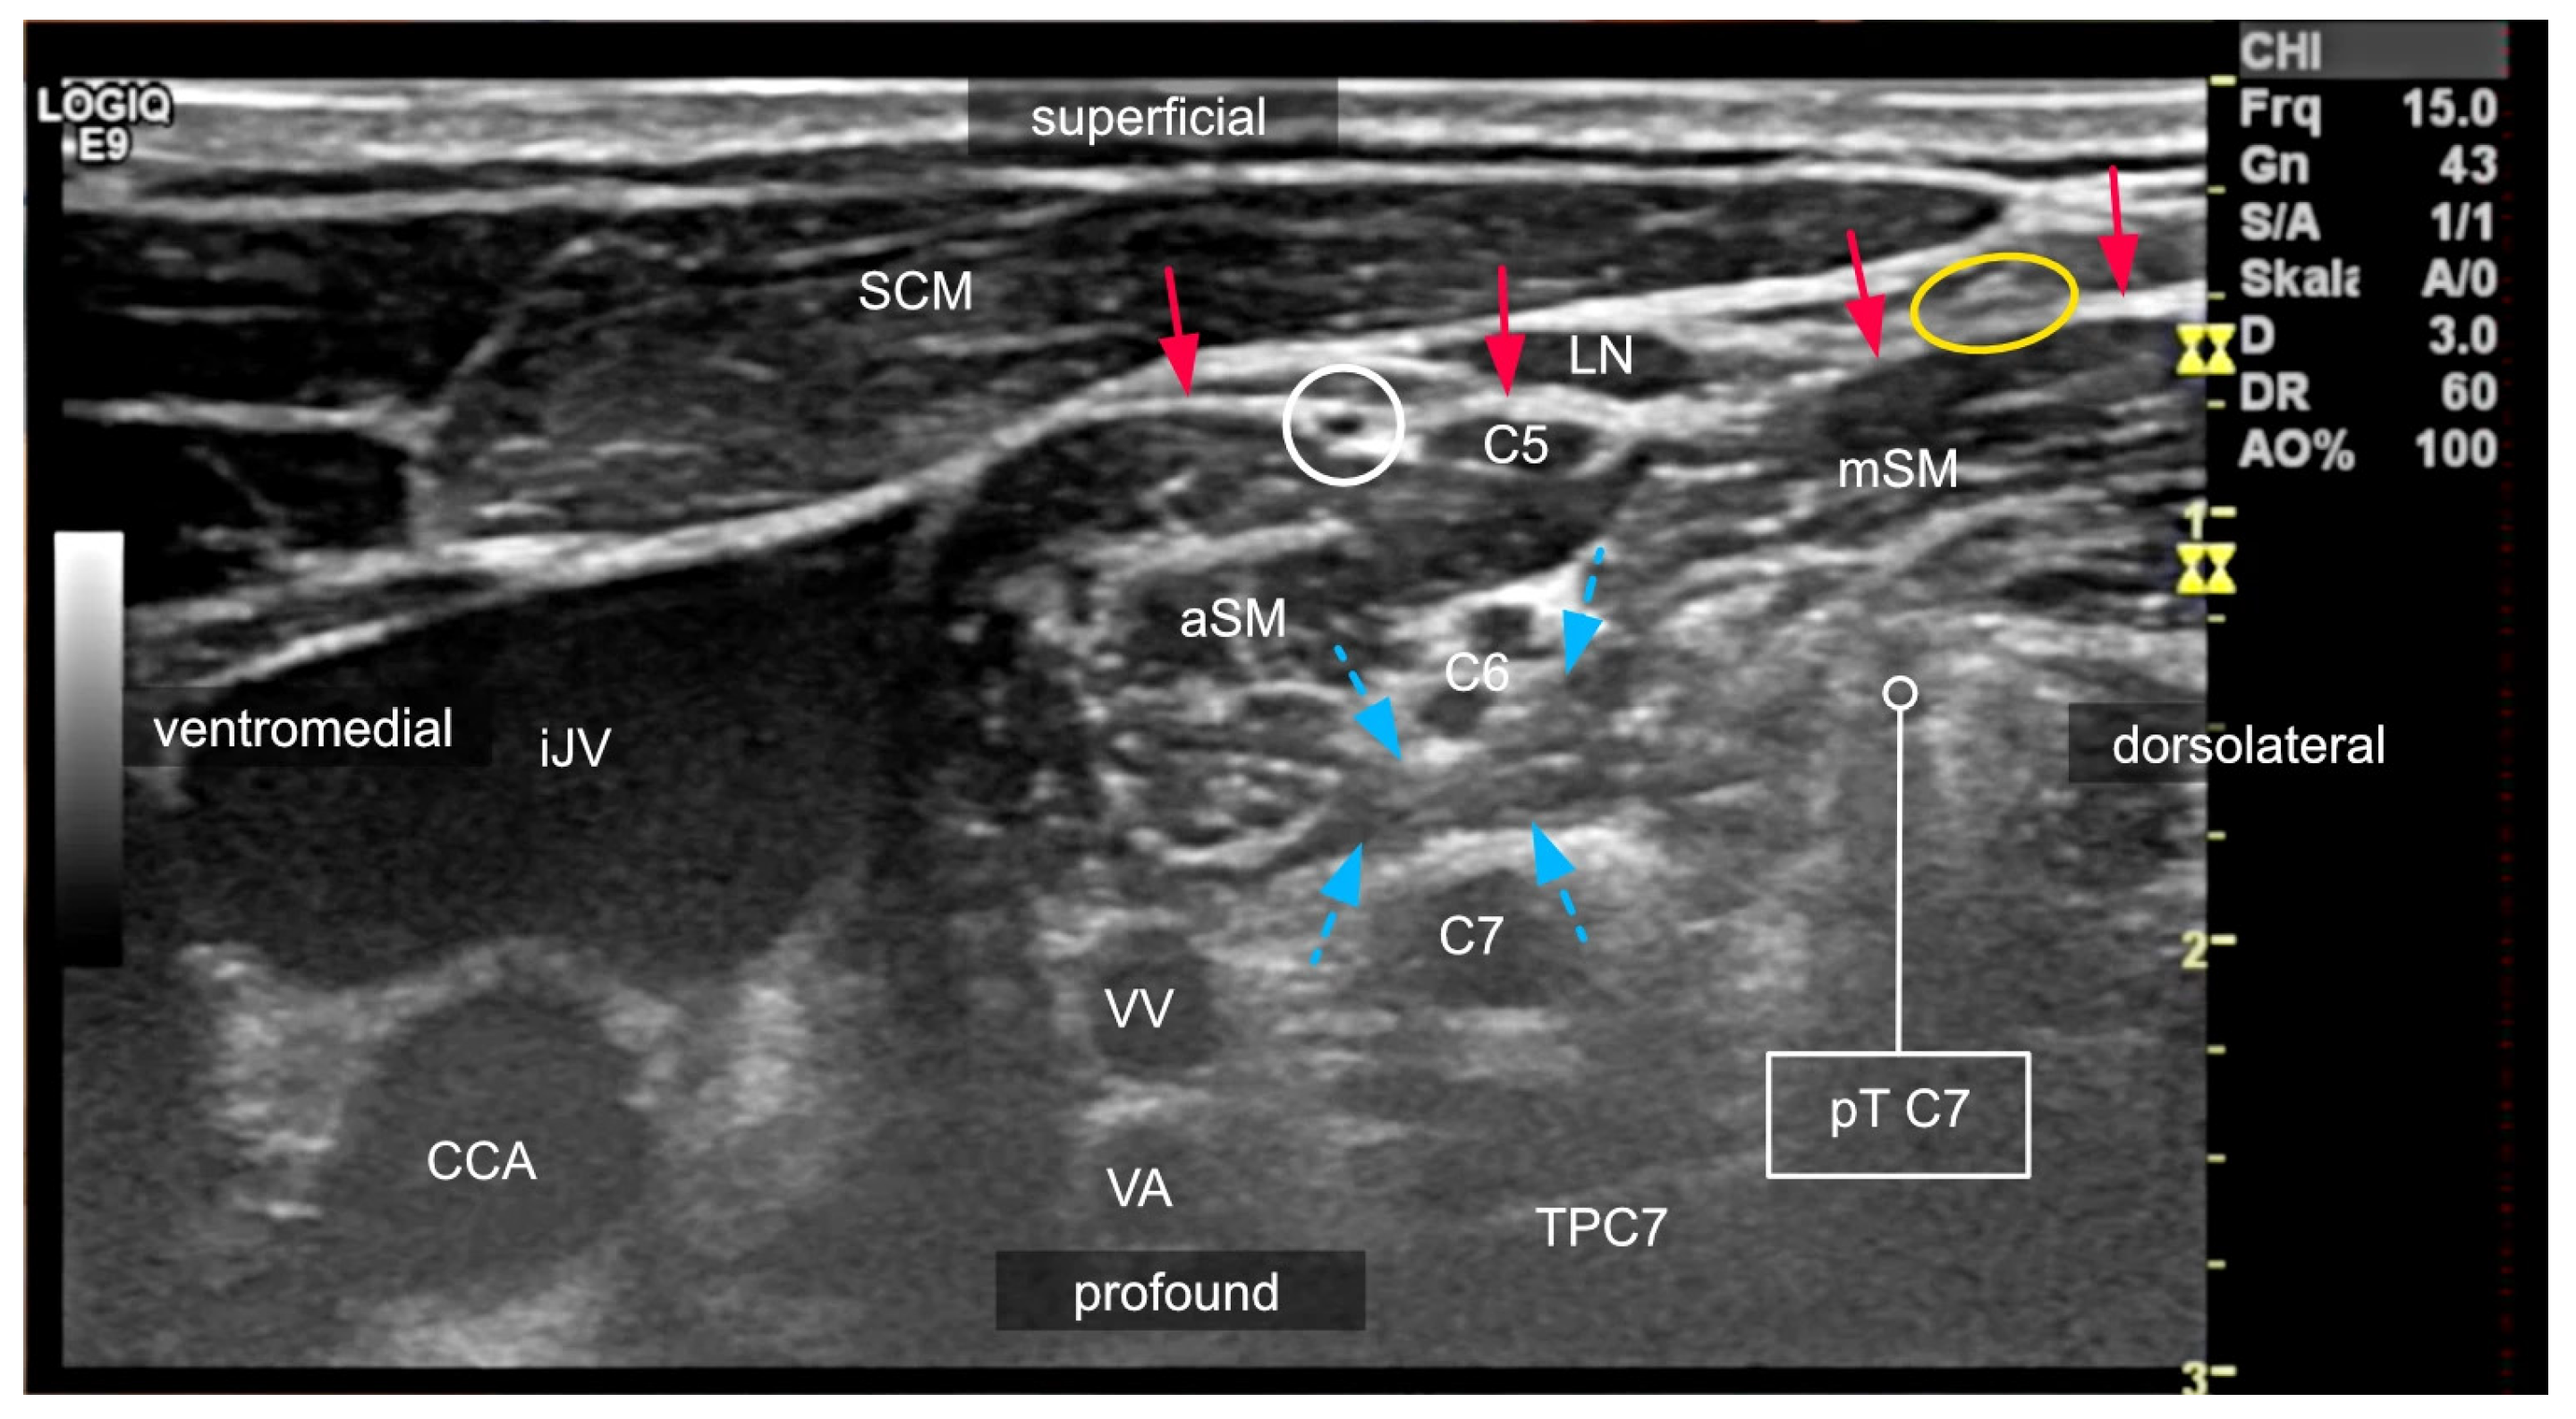

2.2. Anatomical Variations in the Scalene Gap

2.3. Variants of the Course of the Ventral Rami

2.4. Compartments of the Lateral Neck and Their Relevance to Side Effects